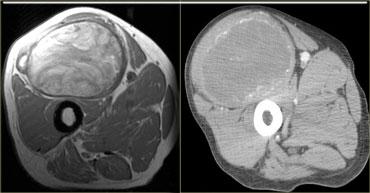

Myositis ossificans

Chấn thương đụng dập nặng gây ra khối máu tụ trong cơ có thể dẫn đến hiện tượng vôi hóa muộn trong mô mềm, được gọi là viêm cơ hóa xương.

Viêm cơ hóa xương có hình ảnh đa dạng tùy thuộc vào mức độ trưởng thành:

Trên MRI, viêm cơ hóa xương có thể khó phân biệt với u xương ác tính (osteosarcoma).

Trên X-quang và CT, có thể thấy hình ảnh vôi hóa mô mềm không gắn liền với xương.

Bên trái là một trường hợp khác của viêm cơ hóa xương với sự hình thành xương.